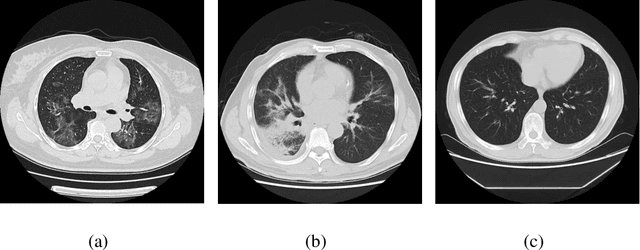

Abstract:We found that the real time reverse transcription-polymerase chain reaction (RT-PCR) detection of viral RNA from sputum or nasopharyngeal swab has a relatively low positive rate in the early stage to determine COVID-19 (named by the World Health Organization). The manifestations of computed tomography (CT) imaging of COVID-19 had their own characteristics, which are different from other types of viral pneumonia, such as Influenza-A viral pneumonia. Therefore, clinical doctors call for another early diagnostic criteria for this new type of pneumonia as soon as possible.This study aimed to establish an early screening model to distinguish COVID-19 pneumonia from Influenza-A viral pneumonia and healthy cases with pulmonary CT images using deep learning techniques. The candidate infection regions were first segmented out using a 3-dimensional deep learning model from pulmonary CT image set. These separated images were then categorized into COVID-19, Influenza-A viral pneumonia and irrelevant to infection groups, together with the corresponding confidence scores using a location-attention classification model. Finally the infection type and total confidence score of this CT case were calculated with Noisy-or Bayesian function.The experiments result of benchmark dataset showed that the overall accuracy was 86.7 % from the perspective of CT cases as a whole.The deep learning models established in this study were effective for the early screening of COVID-19 patients and demonstrated to be a promising supplementary diagnostic method for frontline clinical doctors.